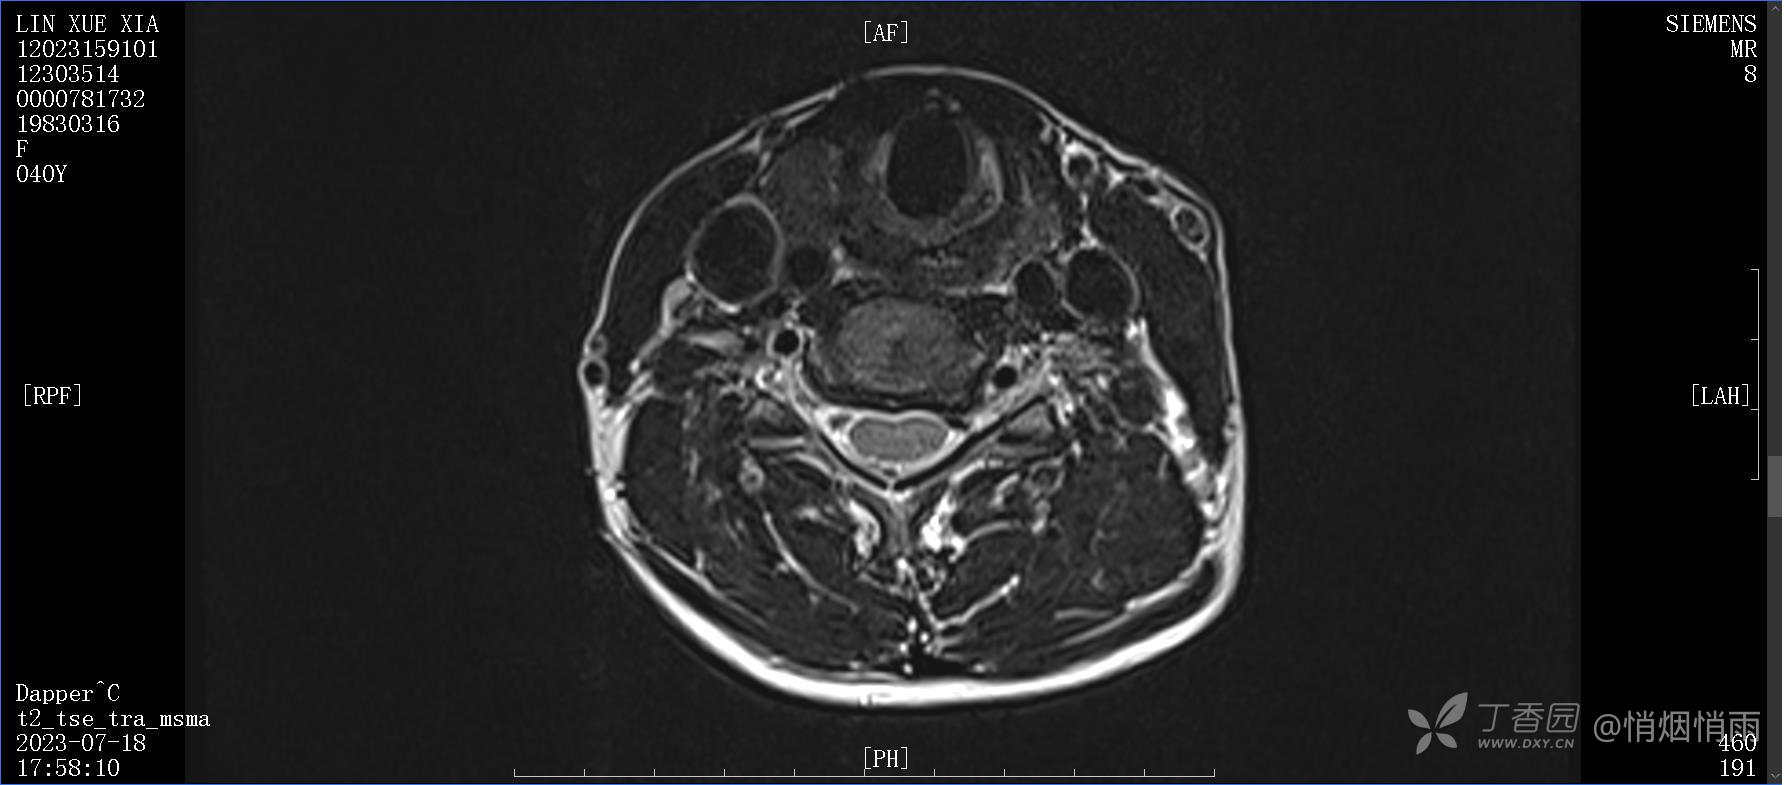

查体:右肩关节局部轻度肿胀,肩胛区压痛明显,痛处不固定,肩关节痛性活动受限,jobe test(+),lift -off test(+),中指、环指感觉较余指减退,余肢端感觉及血运情况可。

目前的诊断,暂时依据辅助检查诊为肩袖损伤,但是患者疼痛的性质和特点,却不是单纯的肩袖损伤所致。考虑过胸廓出口综合征,但是该疾病会出现肩胛区的疼痛吗?(由于考虑到费用的问题,没再进行下一步的检查)带状疱疹会有如此的症状吗?